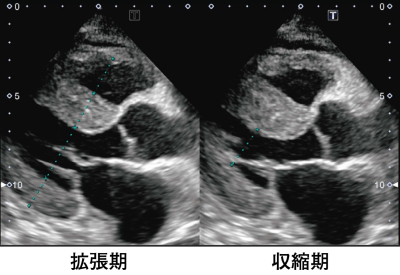

検査所見:尿所見:蛋白3+、糖(-)、沈渣に異常を認めない。血液所見:赤血球 417 万、Hb 13.0 g/dL、Ht 41 %、白血球 6,800、血小板 28 万。血液生化学所見:総蛋白 9.8 g/dL、アルブミン 2.8 g/dL、総ビリルビン 0.7 mg/dL、AST 34 U/L、ALT 26 U/L、LD 345 U/L(基準 176〜353)、ALP 225 U/L(基準 115〜359)、 尿素窒素 18 mg/dL、クレアチニン 2.3 mg/dL、血糖 79 mg/dL、HbA1c 5.3% (基準 4.6〜6.2)、Na 138 mEq/L、K 4.9 mEq/L、Cl 106 mEq/L、Ca 10.8 mg/dL、P 2.1 mg/dL、脳性ナトリウム利尿ペプチド<BNP> 253 pg/mL(基準 18.4 以下)。 CRP 0.1 mg/dL。心電図は心拍数 91/分の洞調律で肢誘導の低電位、左房負荷および不完全左脚ブロックを認める。胸部エックス線写真で心胸郭比は 52 % で、両側に少量の胸水を認める。心エコー図を別に示す。

この患者の心エコーで認められる所見はどれか。

e. 左室壁の著明な肥厚